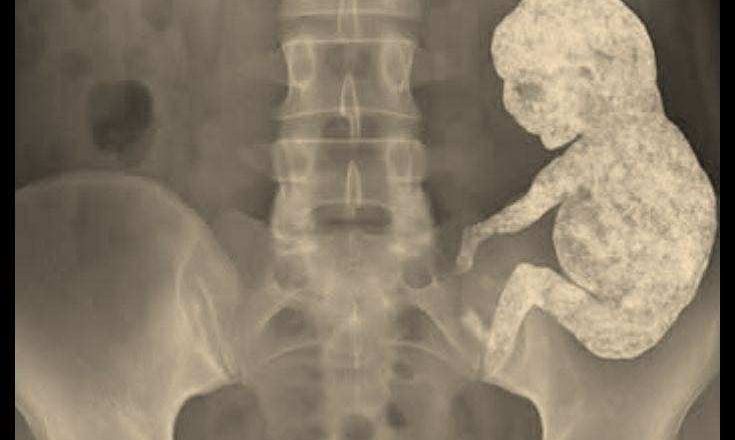

Sur l’écran d’échographie, le médecin se figea. Une masse dure était visible dans l’abdomen de la vieille femme – ronde, entourée de calcium, comme figée dans l’éternité. Un scanner confirma qu’il ne s’agissait pas d’une tumeur. C’était un lithopédion. Un fœtus en pierre.

La lithopédion est un phénomène extrêmement rare, dont même les médecins parlent avec une horreur révérencieuse. Lorsqu’un embryon meurt hors de l’utérus, le corps est incapable de l’expulser. Pour prévenir l’infection, le corps l’enferme dans une coquille de calcium, comme un sarcophage. La nature accomplit l’impossible : elle transforme la mort en pierre.

C’est ainsi que, des décennies plus tard, les chirurgiens prélevèrent soigneusement de son abdomen une petite forme presque parfaite. Un crâne. Des côtes. Un bras minuscule, plié au coude.